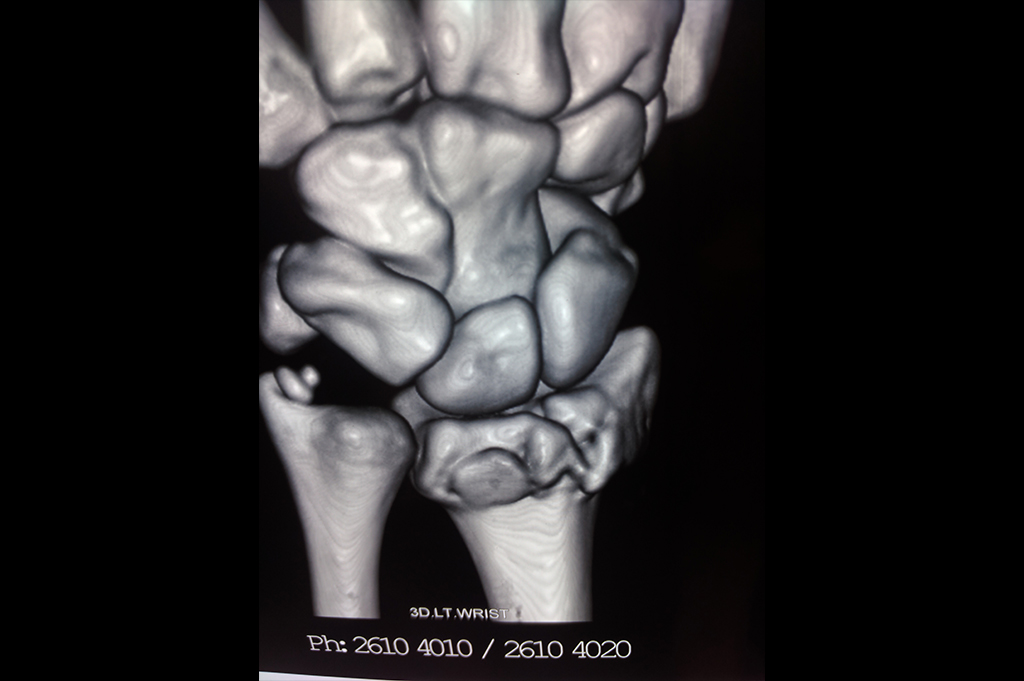

Lower Radius